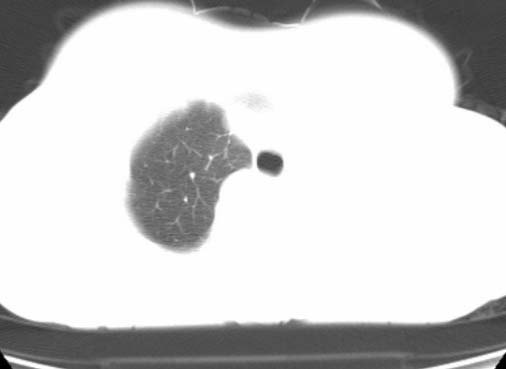

标题: CT25648:求教:是肺发育不全还是结核?

女  20岁。一月前咳血,诊“肺结核”抗痨治疗一月后,咳血停止,现复查。病人精神好。前后ct片对比未见明显变化。既往体检“正常”

1)考虑左肺结核并肺不张、支气管扩张。2)纵隔疝。

以前体检正常只能考虑左肺结核并肺不张、支气管扩张。2)纵隔疝。

考虑左肺结核,左肺毁损,纵膈左偏,既往体检正常不可靠,tb一个月也不会这个样子的,有钙化,应该病程较长,冰冻三尺非一日之寒!

考虑左肺结核,左肺毁损,纵膈左偏,既往体检正常不可靠,tb一个月也不会这个样子的,有钙化,应该病程较长,冰冻三尺非一日之寒

结核,左肺毁损。